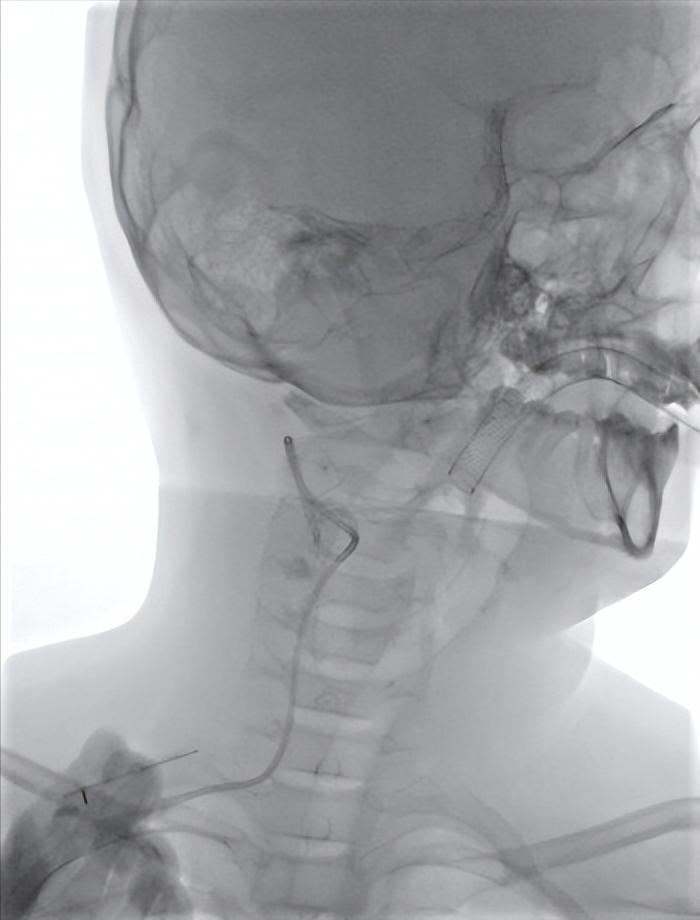

术中置入导丝图片

孩子入院后,完善术前检查,未见明显禁忌,预约第二天手术,手术当天,患儿在全麻的过程中完成了手术,在超声引导下,穿刺包块内最大囊腔,抽出粉红色乳糜液体,在DSA引导下置入泥鳅导丝,引入猪尾导管,将导管末端置入囊腔最低处,经导管造影,可见囊腔显影,后将囊腔内液体全部抽出,约25ml。